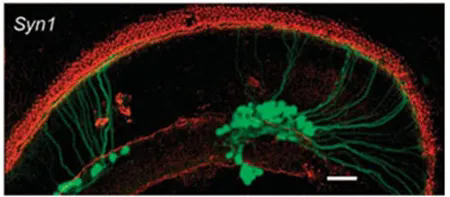

· 特異性啟動子

Syn1(突觸(chu)素1)啟動子可驅動外源基因(yin)在耳(er)蝸(gua)螺旋(xuan)神(shen)經節神(shen)經元中的(de)有效轉(zhuan)導,Myo7a(人肌(ji)球蛋白ⅦA)、Pou4f3(POU結構域第4類轉(zhuan)錄(lu)因(yin)子3)和Slc26a5(溶質載(zai)劑家族26成員5)是轉(zhuan)導毛細胞的(d���e)可選啟動子,使用時應考慮AAV的(de)包裝容量。

圖3. Syn1啟動子驅動����外源基因在(zai)離體培養小鼠耳蝸耳蝸螺(luo)旋神經(jing)節神經(jing)元中(zhong)的表達(da)

(Askew C, et al.Sci Transl Med.2015)